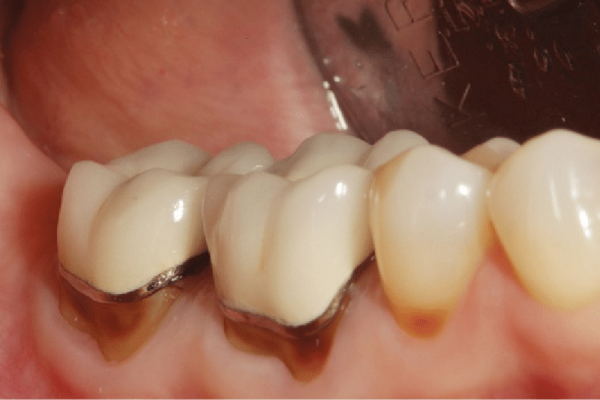

Bac si tay nghe kem se de mai rang sai ty le, khien rang su lech khoi rang that-100

Bác sĩ không có đủ kinh nghiệm chuyên môn trong việc lên phác đồ điều trị phù hợp. Việc mài cùi răng không đúng cách trong quá trình bọc sứ có thể làm mất sự sát khít giữa răng sứ và thân răng thật, tạo kênh và cộm, dẫn đến hở viền lợi. Sự chủ quan trong việc chẩn đoán tình trạng răng miệng trước khi thực hiện bọc răng sứ cũng có thể dẫn đến tụt lợi do bệnh lý không được chữa trị kịp thời.

Việc áp dụng kỹ thuật lấy dấu răng không đúng cũng góp phần tạo ra sai số và ảnh hưởng đến quá trình chế tác răng sứ. Khi lắp răng, sự không sát khít giữa mão răng sứ và cùi răng tạo ra kẽ hở, gây thuận lợi cho vi khuẩn và mảng bám tích tụ, tạo điều kiện cho các vấn đề về sức khỏe nướu và tụt lợi.